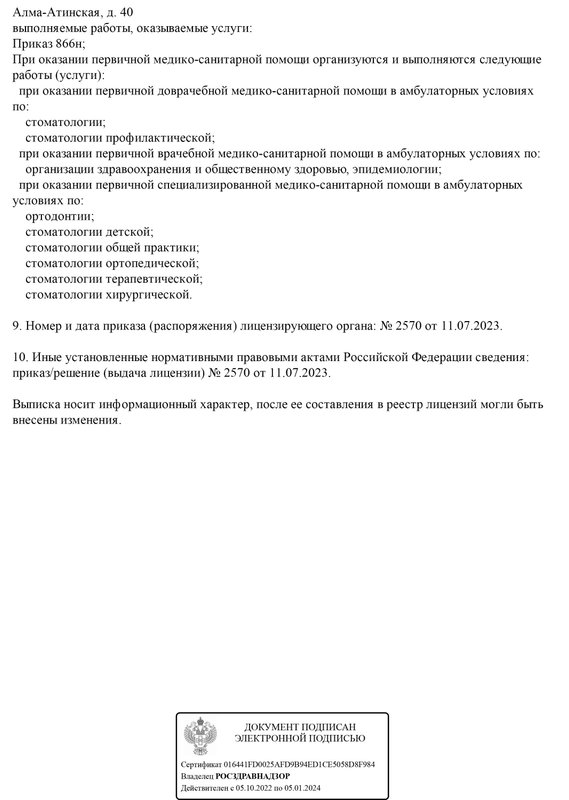

Лицензии, награды, сертификаты